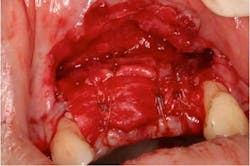

Fig. 2